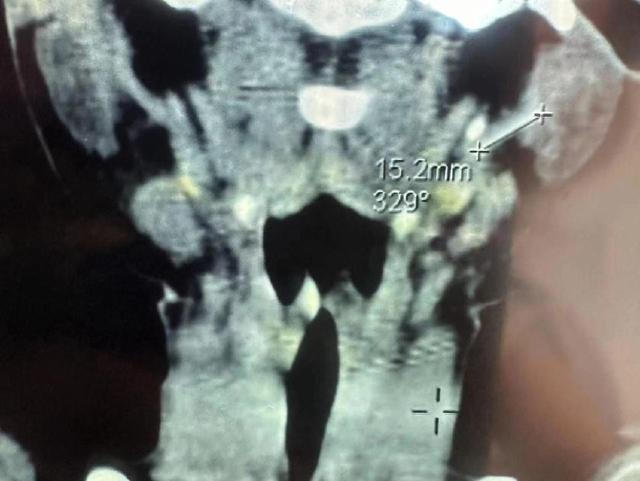

今年3月,白海海带孩子再次来到北京儿童医院,这次B超,针头导管又找不见了,做CT要等一周,孩子那几天一直在生病,无奈他们又回到了榆林。4月7日,在榆林市星元医院做CT,这次清晰地看到,15.2mm的异物在左侧颈部,“前几年找不上,医院认为我们难为他们,这次找到了,医院也不得不承认了。”

4月7日,星元医院给桐桐拍的CT影像显示,左侧颈部可见15.2mm异物。

形似针状的异物长达15.2mm